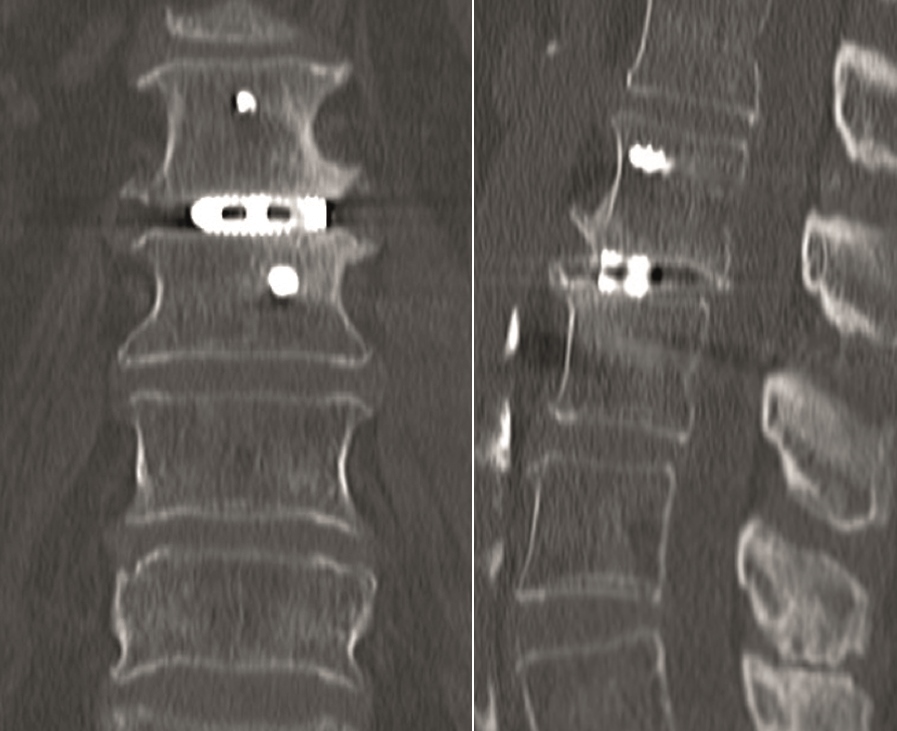

Case 5 : Degenerative scoliosis

A female patient 66-years-old with back pain, leg pain, and degenerative deformity. The x-rays show left convex degenerative scoliosis Cobb T12-L3 38. Nonoperative treatment failed. Treatment option was posterior fusion T11-L5, with URS Facet Wedge L2-L3 unilaterally.

A conventional approach for posterior correction was taken, with indirect Foraminal decompression and Facet Wedge fusion (apex curve). Facet Wedge introduction after curve correction with rod in situ. X-ray follow-up initially (Fig 20), with CT assessment of Facet Wedge fusion after 6 months (Fig 21).